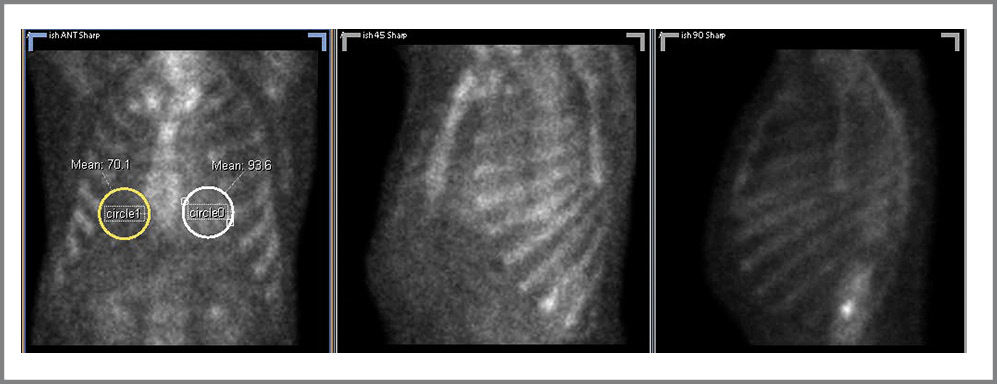

Оценку соотношения накопления РФП в проекции миокарда по отношению к контралатеральной стороне (H/Cl) производили на планарном изображении в передней проекции путем создания зоны интереса (ROI) круг-лой формы, помещения его на область ЛЖ, копирования и отзеркаливания ROI на другую сторону грудной клетки с подсчетом частного от средних значений числа импульсов в пикселе в пределах обоих ROI (рис. 1). Ориентировочной пороговой величиной H/Cl для определения TTR-амилоидоза было принято значение ≥1,5 [13].

Рис. 1. Расположение ROI при вычислении параметра H/Cl. У данного пациента H/Cl=93,6/70,1=1,33. / Fig. 1. Location of the ROI when calculating the H/Cl parameter. This patient has H/Cl=93.6/70.1=1.33.